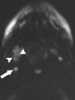

Necrotic lymph node metastasis

Lymphadenopathy or adenopathy is a disease of the lymph nodes, in which they are abnormal in size or consistency. Lymphadenopathy of an inflammatory type (the most common type) is lymphadenitis, producing swollen or enlarged lymph nodes. [Source: Wikipedia ]